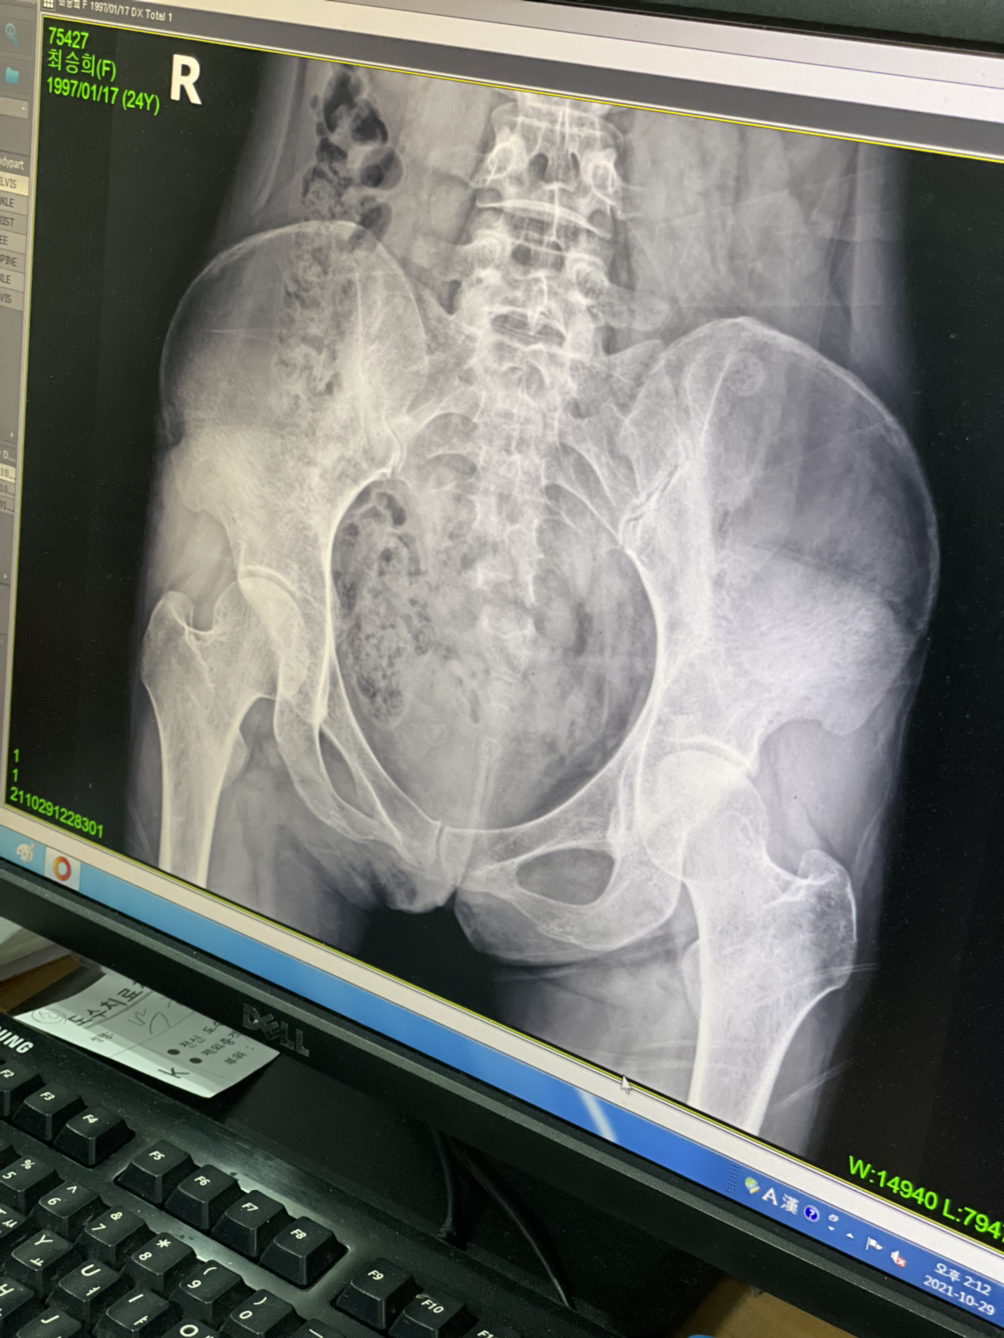

골반이 삐뚤어졌대

종형외과...

넘비싸...8ㅅ8 근데 너무아프고...ㅋㅋㅋ 많이 삐둘어지긴한듯